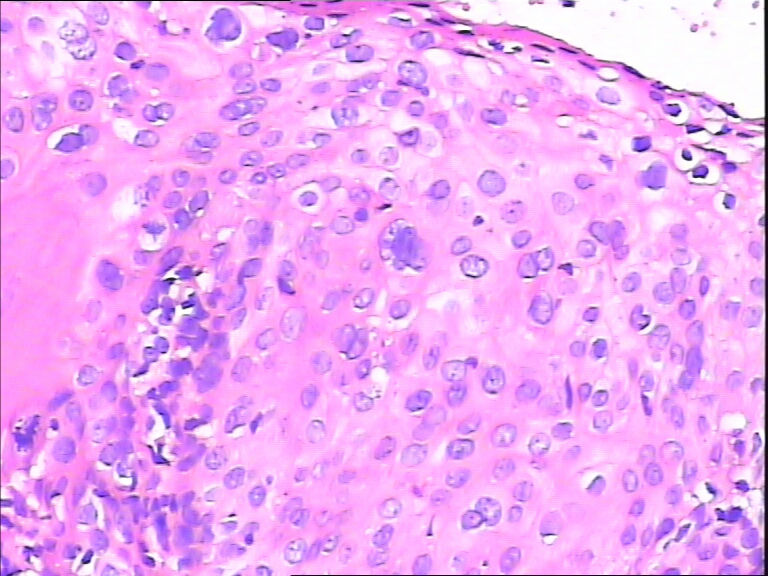

45y,触血,宫颈多点活检。

HPV感染

不同级别的CIN,局灶已达到CIN3。

HPV感染。局部已达到CIN2-3

CINⅡ,提示HPV感染。

HPV感染。灶性CIN2-3